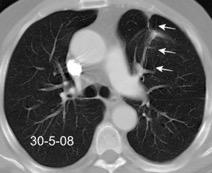

VIH+. 1 mes antes derrame pleural en el curso de una

infección

Huggins